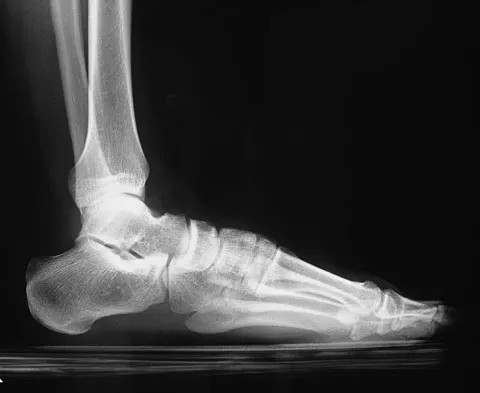

A 42-year-old woman sustained a closed, displaced talar neck fracture in a motor vehicle accident. Which of the following is an avoidable complication of surgical treatment?

Explanation

Malunion of the talus is a devastating complication that leads to malpositioning of the foot and subsequent arthrosis of the subtalar joint complex. This is considered an avoidable complication in that accurate surgical reduction will minimize its development. Posttraumatic arthritis of the subtalar joint, osteonecrosis of the talus, posttraumatic arthritis of the ankle joint, and complex regional pain syndrome all may develop as a result of the initial traumatic event and may not be avoidable despite anatomic reduction. Rockwood and Green's Fractures in Adults, ed 5. Philadelphia, PA, Lippincott, Williams and Wilkins, 2001, pp 2091-2132.

- Daniels TR, Smith JW, Ross TI: Varus malalignment of the talar neck: Its affects on the position of the foot and on subtalar motion. J Bone Joint Surg Am 1996;78:1559-1567.